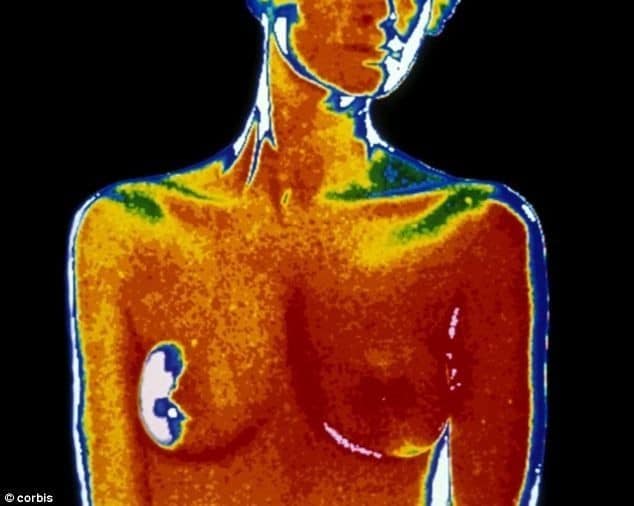

Un dépistage inadapté au génie évolutif de la maladie, condamné à l’inefficacité

Inadapté à l'histoire naturelle du cancer du sein, le dépistage est-il voué à l'échec? Par Bernard Duperray